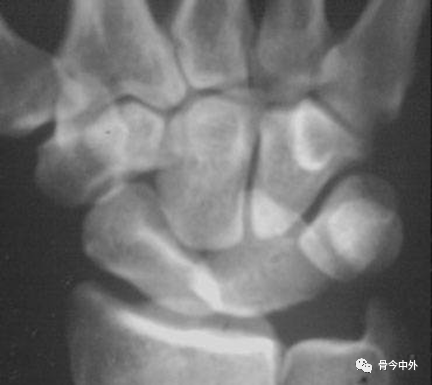

图1 成人期腕关节正侧位及舟骨蝶位片。1.舟骨;2.月骨;3.三角骨;4.豆状骨;5.大多角骨;6.小多角骨;7.头状骨;8.钩骨;9.桡骨茎突;10.尺骨茎突;11.第一掌骨基部。